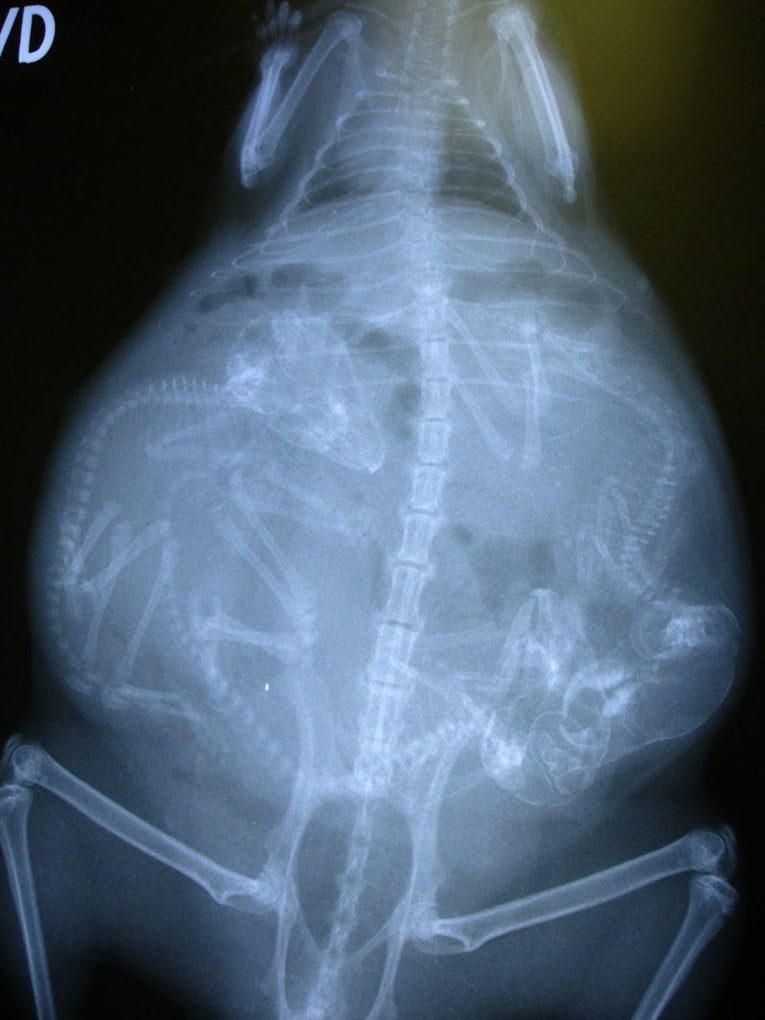

Беременная собака